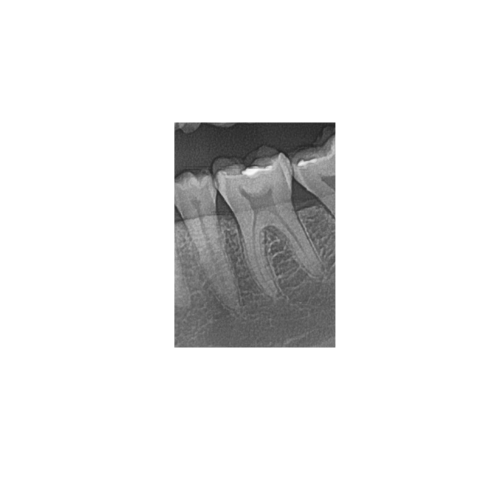

A panoramic dental scan (also known as an OPG or orthopantomogram) provides a broad, single-image view of your entire upper and lower jaws, all the teeth, the jaw joints (TMJ) and surrounding bone structures. It is highly valuable for:

- Assessing wisdom-teeth position, impactions, crowding.

- Planning orthodontic treatments/braces and evaluating tooth development.

- Screening for bone-loss, jaw-joint disorders, cysts or tumours in the maxillofacial region.